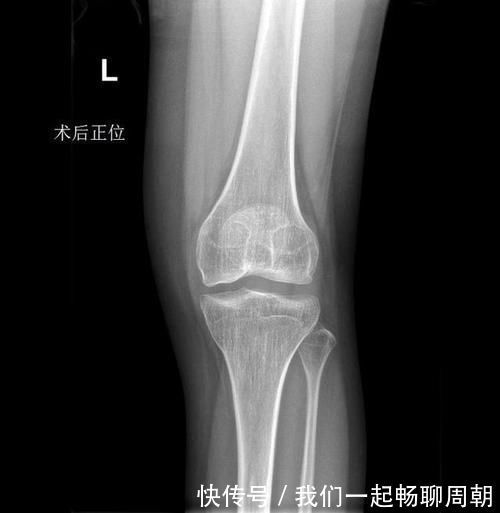

x光片|左边膝盖疼了1年多,结果查出来这一系列问题

今年21岁的小程,正在广州读大三,一年前小程在参加运动会时伤到了膝盖,本以为稍作休息就能有所缓解,但是左膝疼痛断断续续维持了一年多,直到最近一个月病情越发严重。

通过一系列的检查,前十字韧带松弛(左膝关节前交叉韧带损伤)、陈旧性膝外侧副韧带损伤(左侧)、滑膜炎(左膝)、膝关节积液(左侧)、左胫骨平台囊肿。

在排除了手术的禁忌症的情况下,我们为小程做了左膝关节镜检治疗术,术中见:

1)关节腔内滑膜轻度增生、充血。

2)探查左膝内、外侧半月板,可见外侧半月板轻度磨损,外侧半月板边缘毛糙,但无明显撕裂;内侧半月板未见明显损伤。

3)股骨外侧髁软骨面未见明显损伤;股骨内侧髁软骨面可见软骨软化,内侧髁外侧可见轻度磨损。

4)探查前、后交叉韧带、腘肌腱,可见后交叉韧带股骨侧止点变异,偏向于软骨侧,前后交叉韧带距离较近,相互摩擦,前交叉韧带部分损伤,剩余部分张力可,探查可见轻度松弛,考虑无需行前交叉韧带重建。

5)探查膝关节腔,髁间窝较正常狭窄约3-5mm左右。予以刨刀清理关节腔内增生、充血的滑膜组织。